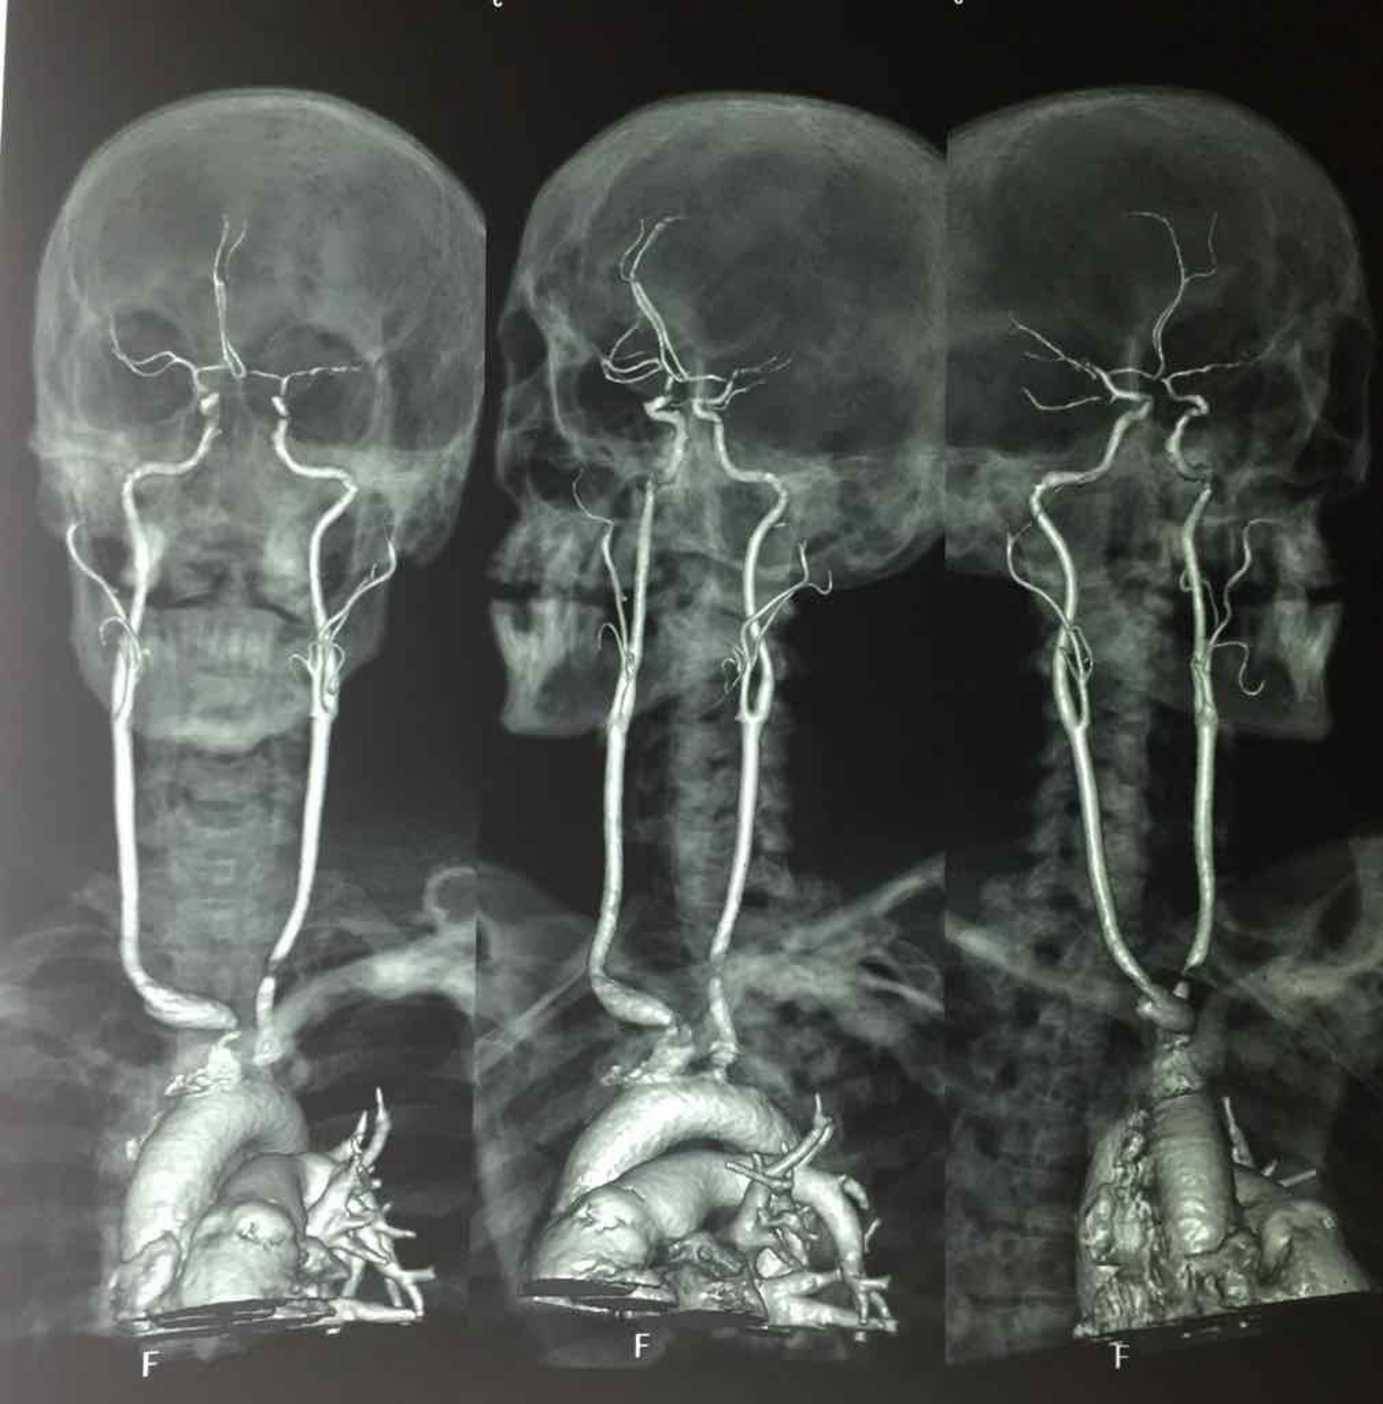

Every day, tens of thousands of doctors, nurses and paramedics, as well as students in all three professions, fire up Figure 1 to tune in to conversations just like this one. Scroll through the smartphone app and you’ll find thousands of photos of tumours, mangled limbs and inexplicable blotches, as well as ECG readings, scans and X-rays.

Stripped of any form of patient-ID information, each post becomes a launching pad for discussion among wired health professionals who, it would appear, have an insatiable appetite for digital shop-talk in the form of rapid-fire comment strings about what’s going on in these visceral images.